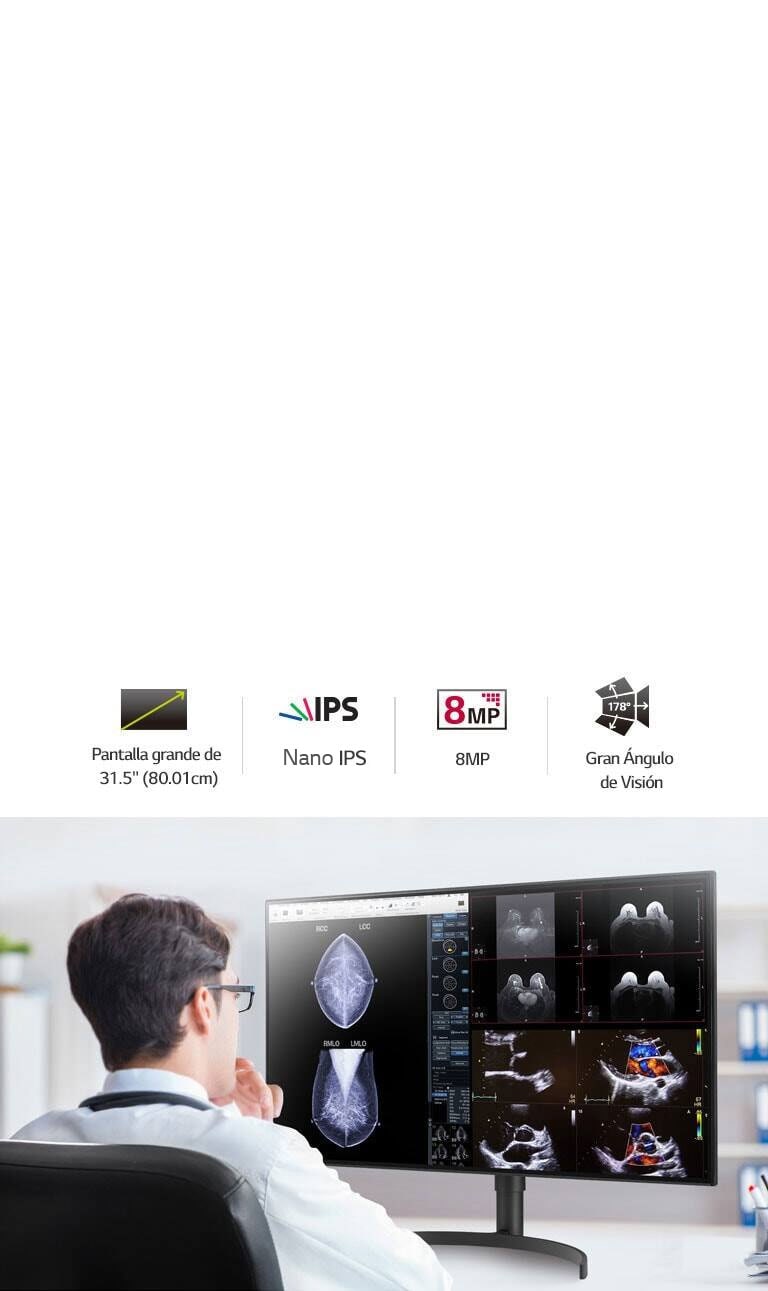

Para Aumentar la Eficiencia y

Comodidad

PANTALLA

Tamaño [Pulgada]

31.5

Ángulo de visión (CR≥10)

178º(D/I), 178º(Arriba/Abajo)